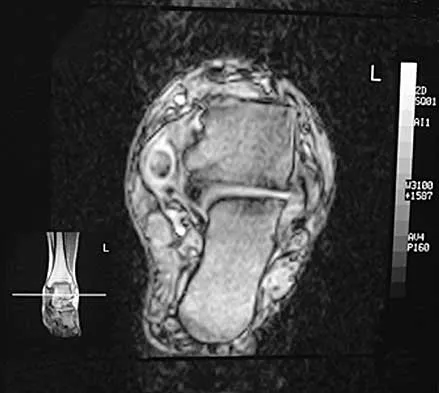

A 47-year-old woman has had medial ankle pain and swelling for the past 3 months. She recalls no specific injury, and casting and nonsteroidal anti-inflammatory drugs have failed to provide relief. Examination reveals a pes planus with heel valgus that is passively correctable. Radiographs show no evidence of arthritis. An MRI scan is shown in Figure 16. What is the most appropriate surgical procedure to alleviate her pain?

Explanation